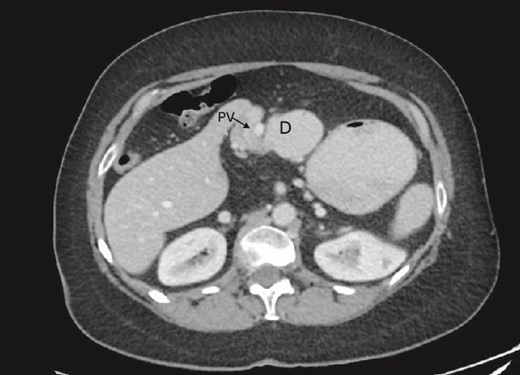

On examination, the abdomen was soft but mildly distended. Bowel sounds were heard, and the epigastrium was mildly tender. Standard bloodwork was normal. Review of an abdominal computerized tomography (CT) scan from 4 years prior showed congenital malrotation of the bowel, with the small bowel to the left of the midline and colon entirely to the right (Fig. 1). There was partial agenesis of the dorsal pancreas (Fig. 2), azygous continuation of the inferior vena cava (IVC), a retroaortic and retrocrural left renal vein, and an unremarkable spleen alongside some splenules. The PV traversed anterior to the first part of the duodenum (Fig. 3). There was relative narrowing of the distal stomach and the duodenum was nondilated.

Preduodenal PV seen crossing the duodenum (D) causing partial obstruction.

A PDPV needs special consideration during duodenal and biliary tract surgery as there is an increased risk for ligation, tearing, division, and thrombosis due to excessive handling [1]. This is especially important during emergent laparotomy where cross-sectional imaging may not be performed prior to surgery. In our case, a CT scan was beneficial as the PDPV was readily visible traversing anterior to the duodenum and identifiable as a potential cause of duodenal obstruction. This was further confirmed during EGD when there was difficulty passing the gastroscope into the first part of the duodenum. This approach is similar to previous case reports where CT imaging and an EGD were performed prior to surgery [11, 12].